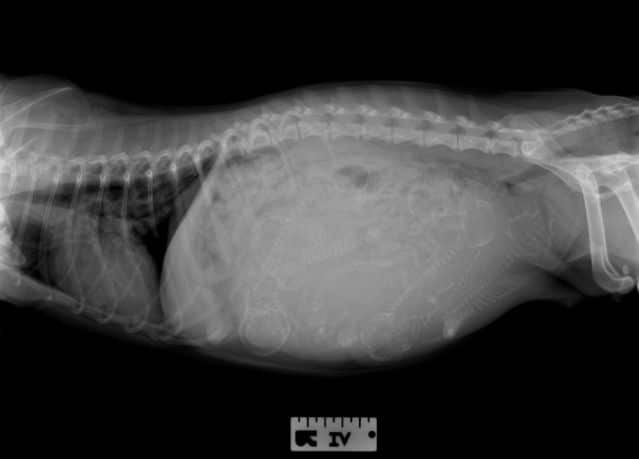

Radiographs

Radiographs (X-Rays) are not helpful in pregnancy diagnosis until a minimum of 45 days into pregnancy, which is when the skeleton has started to mineralize. Without timing, this can be very difficult to determine. Radiographs are recommended for the week before whelping for the most accurate puppy count.